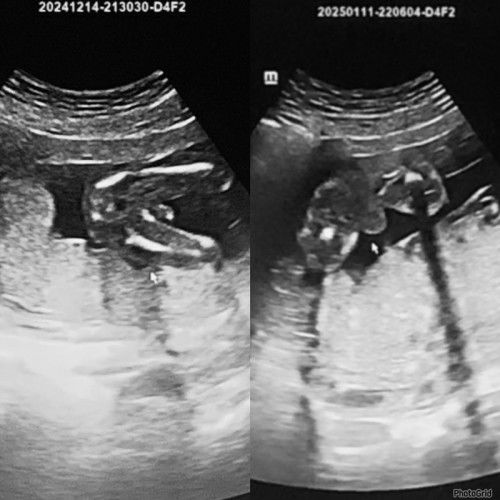

Scan Baby 17 weeks & 21 Weeks

hi mommy berpengalaman, kat gambar scan ni nampak lebih kpd girl or boy ye ? doc kata baby boy tapi tk nampak bebird. Confius saya 😅 excited nk beli baju baby . Belah kiri scan masa 17weeks belah kanan 21weeks. Baby boleh berubah jantina ke ye dah hujung2 due nanti. TQ mommy #mohonbantujawabbunda